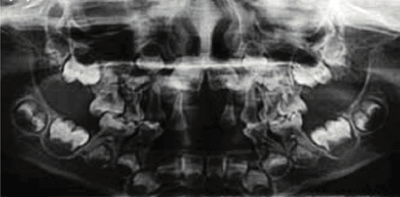

Radiograph showing enlarged pulp chambers and shape abnormalities.

Dental manifestations of hypophosphatasia in children and the effects of enzyme replacement therapy on dental status: A series of clinical cases by Larisa Kiselnikova is licensed under CC BY 4.0.

Delayed eruption of permanent teeth

Early loss of baby teeth with

root intact